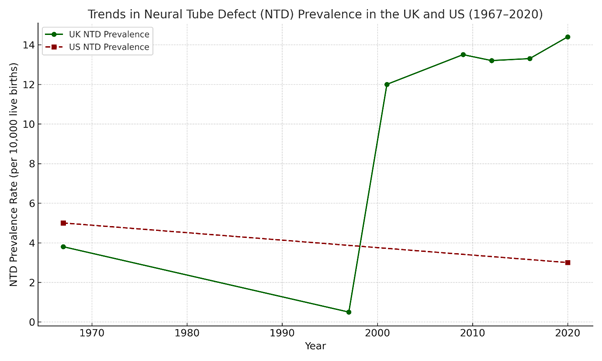

United Kingdom (UK) NTD Birth Trends:

- 1936–1956: NTD prevalence fluctuated between 1.54 and 2.8 per 1,000 births. (Bower, C. and Stanley, F.J., 2004)

- 1965–1997: NTD prevalence declined by 96%, dropping from 3.80 per 1,000 births in 1965 to 0.14 per 1,000 in 1997. This sharp decline has occurredbefore folic acid fortification is introduced. (McDonnell, R. et al.,1999)

- 1991–2011: Prevalence remained relatively stable, with 2011 rates like 1991. No significant further reduction was observed. (EUROCAT/BMJ, 2015).

- 2011–2021: Recent data indicates that NTD prevalence has slightly increased, contradicting expectations that folic acid fortification would further reduce cases.

- 2010-2014, prevalence was 12.1 per 10,000 total births in Scotland (Stockton, D. et al., 2025).

- 2015-2019, prevalence increased to 13.6 per 10,000 total births. (Best et al., 2024).

- In Scotland (2021), NTD prevalence was 14.3 per 10,000 births, suggesting a continued rise. (Stockton et al., 2025)

NTDs declined significantly before folic acid fortification, largely due to the removal of teratogenic drugs and improved prenatal care. However, recent increases in NTD rates suggest that folic acid fortification has not led to further reductions, raising concerns about its long-term effectiveness.

United States (US) NTD Birth Trends:

A 2016 study released by Stanford Medicine and covered by Erin Digitale, titled “Less decline than expected in rate of brain, spine defects after folic acid fortification program”, claimed that folic acid fortification had reduced neural tube defects (NTDs), but that the decline had since slowed (Digitale, 2016).

United States (US) NTD Birth Trends: (Centers for Disease Control and Prevention, 2015; CDC, 2023; Mai et al, 2024):

Analysis of publicly available CDC data (2015–2024) reveals a complex trend in neural tube defect (NTD) rates that does not align with claims of uniform decline following folic acid fortification. Instead, recent findings indicate fluctuations in prevalence, raising critical questions about data interpretation and the attribution of causality.

Before folic acid fortification (pre-1998)

- Prior to mandatory folic acid fortification, NTD rates varied significantly by region.

- Estimated spina bifida prevalence was ~5 per 10,000 births in the general population.

After folic acid fortification (1998–Present)

- Following the 1998 fortification mandate, NTD prevalence reportedly dropped by ~28%, with spina bifida rates declining to 3.5 per 10,000 births.

- However, post-2010 data suggests a slowing of decline, with some areas showing plateauing or even slightly rising trends.

The initial reduction in NTDs post-fortification suggests some benefit, but data from 2010 onwards raises questions about whether long-term trends are influenced by fortification alone. Other factors – such as improved prenatal care and reduced use of teratogenic medications – may have played a larger role than acknowledged.

5.6 Did Folic Acid Fortification Really Cause the NTD Decline?

The key question: If NTDs had already declined by over 90% before folic acid fortification, how can policymakers claim that fortification was responsible for the drop?

- In the UK, NTDs dropped from 3.80 per 1,000 births (1965) to 0.14 per 1,000 (1997) – before folic acid fortification was introduced (Wald et al., 2001; Botto et al., 2005).

- In the US, NTDs had been declining for decades before the 1998 fortification mandate (CDC, 1995; Williams et al., 2002).